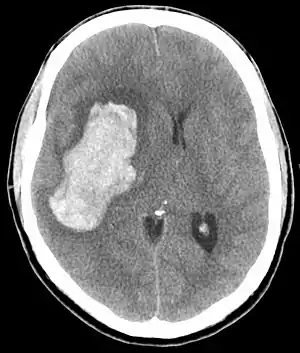

| CT scan depicting intracranial hemorrhage, a possible complication of hypertensive emergency. Patients with spontaneous intracranial hemorrhage present with newfound headache and neurologic deficits. | |

In the brain, hypertensive encephalopathy - characterized by hypertension, altered mental status, and swelling of the optic disc - is a manifestation of the dysfunction of cerebral autoregulation. Cerebral autoregulation is the ability of the blood vessels in the brain to maintain a constant blood flow. People who suffer from chronic hypertension can tolerate higher arterial pressure before their autoregulation system is disrupted. Hypertensives also have an increased cerebrovascular resistance which puts them at greater risk of developing cerebral ischemia if the blood flow decreases into a normotensive range. On the other hand, sudden or rapid rises in blood pressure may cause hyperperfusion and increased cerebral blood flow, causing increased intracranial pressure and cerebral edema, with increased risk of intracranial bleeding.[4]

Consequences of hypertensive emergency result after prolonged elevations in blood pressure and associated end-organ dysfunction. Acute end-organ damage may occur, affecting the neurological, cardiovascular, kidney, or other organ systems. Some examples of neurological damage include hypertensive encephalopathy, cerebral vascular accident/cerebral infarction, subarachnoid hemorrhage, and intracranial bleeding. Cardiovascular system damage can include myocardial ischemia/infarction, acute left ventricular dysfunction, acute pulmonary edema, and aortic dissection. Other end-organ damage can include acute kidney failure or insufficiency, retinopathy, eclampsia, and microangiopathic hemolytic anemia.